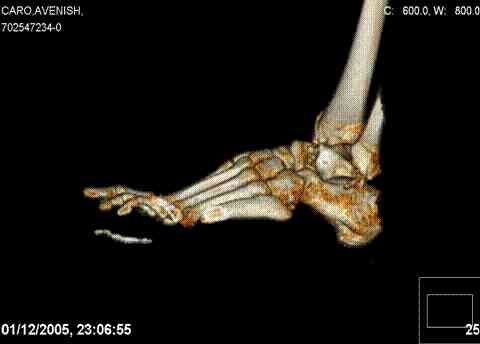

[Ortho] Осколчатый перелом таранной кости [1/2]

ya by popytalsya sobrat talus anatomichno,seichas pozdno operirovat

iz za oteka,po etomy distrakziya apparatom budet optmalna.Posyalu vam

podobyai moi sluchai.